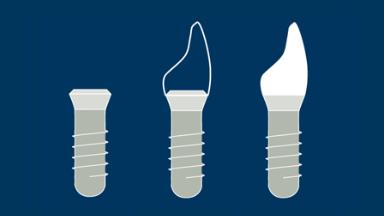

O momento em que os implantes são colocados em função é marcado pela conexão da prótese ao implante. A escolha do protocolo de carregamento mais adequado é um passo importante no processo de planejamento do tratamento. Ao selecionar o momento da reabilitação com implante, você se depara com uma importante decisão clínica. Este módulo apresenta os diferentes critérios para escolher os protocolos de carregamento.

- listar as definições de protocolos de carregamento de implantes imediatos, precoces e convencionais

- selecionar o protocolo de carregamento apropriado de acordo com diferentes situações clínicas